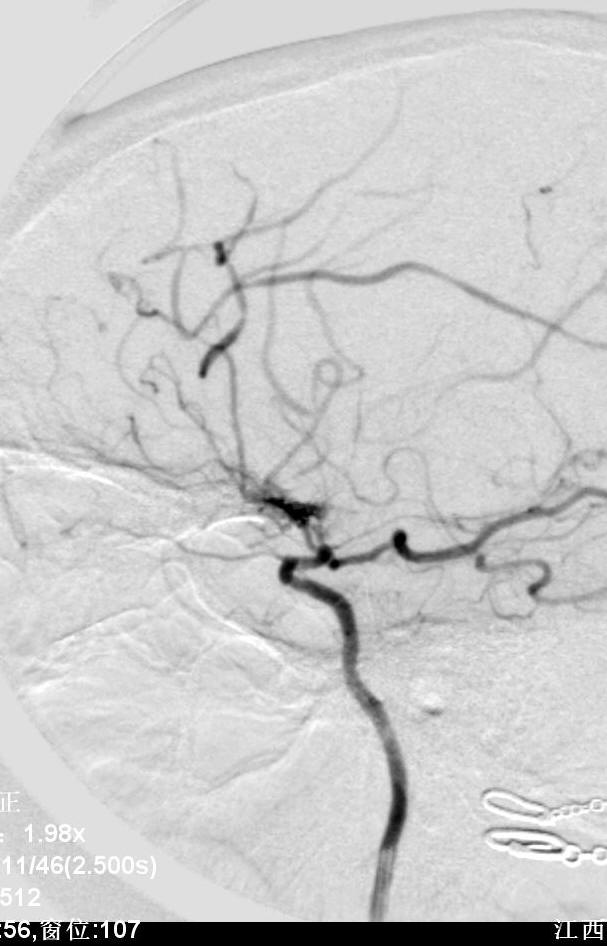

病例4